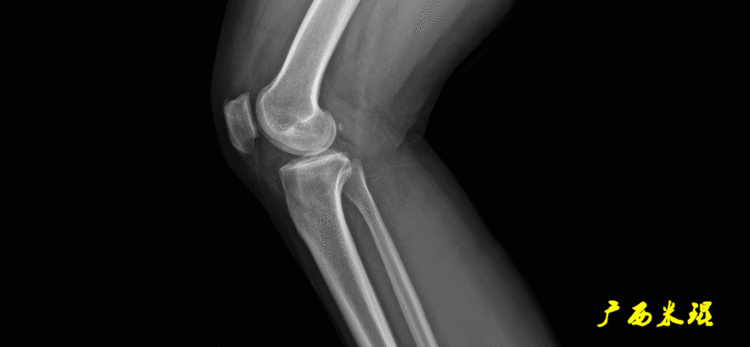

(2)股骨远端关节线正位为股骨内外侧髁最低点之间的连线。髌骨下极在此线之上,距离大于20mm可考虑为高位髌骨。

侧位为连接股骨髁与干骺端相交两点的连线,这个线用得很少。

(3)胫骨近端关节线正位为胫骨内外侧平台最低点之间的连线。

侧位为沿胫骨平台软骨下骨平面的直线,通常与胫骨干有10°±2°的后倾。

说明一下,膝关节线常常为膝关节间隙的水平线,也是膝关节的轴线,只有在比较正常的关节情况下使用,大多数情况下画出股骨远端机胫骨近端的关节线更好。(4)踝关节线踝关节线为胫骨远端软骨下骨之间的连线。

胫骨近端后倾角(PPTA):胫骨平台关节面有平均10°的后倾,其中内侧后倾约12°,外侧后倾约7°。矢状面上胫骨平台的切线与胫骨解剖轴形成的夹角叫胫骨近端后倾角,正常为80°±3°。